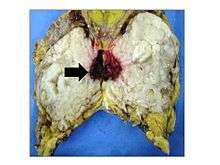

Classification

Phyllodes tumors are a fibroepithelial tumor composed of an epithelial and a cellular stromal component. They may be considered benign, borderline, or malignant depending on histologic features including stromal cellularity, infiltration at the tumor's edge, and mitotic activity.[1] All forms of phyllodes tumors are regarded as having malignant potential. A large series from the M.D. Anderson Cancer Centre reported the incidence of each as benign (58%), borderline (12%), and malignant (30%). Malignant phyllodes tumours behave like sarcomas and can develop blood-borne metastases. Approximately 10% of patients with phyllodes tumours develop distant metastases and this can go up to 20% in patients with histologically malignant tumours.[2] The commonest sites for distant metastases are the lung, bone, and abdominal viscera. Rare sites of metastasis like to parotid region have also been described.[3]